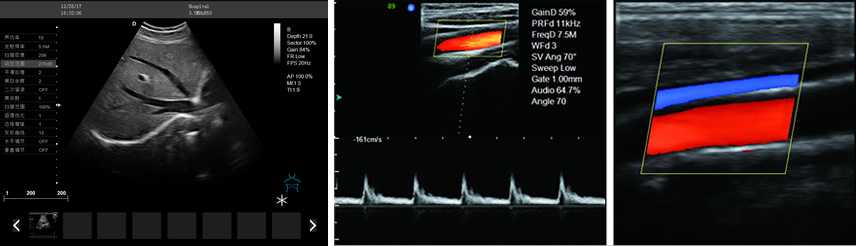

DW-PF522

彩色多普勒

產(chǎn)品性能:高集成數(shù)字式彩色多普勒技術(shù),寬頻探頭,強(qiáng)勁的組合式模塊化軟件設(shè)計(jì),全數(shù)字式大容量圖像存貯和文件歸檔管理,適用范圍:用于人體超聲診斷檢查。